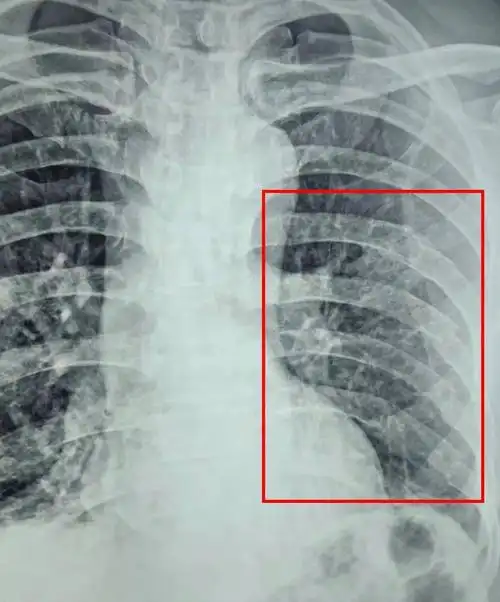

[每周胸片] 233 多发性陈旧性肋骨骨折,能看清楚是那几根肋骨骨折吗?